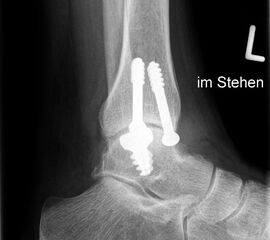

Eine vorausgehende Arthroskopie ist zu empfehlen. Zum Einbringen des Implantates ist eine Osteotomie des medialen Malleolus erforderlich.

Zum Lesen der Bildbeschreibung und zur Vollansicht bitte die Bilder anklicken. Bilder: Christoph Becher.

Abschließend erfolgt die Osteosynthese des medialen Malleolus und der schichtweise Wundverschluss. Anschließend Anlegen eines sterilen Wundverbandes sowie Ruhigstellung in einer Gipslonguette in Neutralstellung.

CAVE: Bei der postoperativen Röntgenkontrolle muss bedacht werden, dass die Knorpelschicht nicht abgebildet ist. Da das Implantat bei einer korrekten Positionierung unterhalb des Knorpelniveaus die knöcherne Fläche dennoch etwas überragt, kann dies zu einer Fehlinterpretation führen, dass das Implantat übersteht.

Zum Lesen der Bildbeschreibung und zur Vollansicht bitte die Bilder anklicken. Bilder: Sarah Ettinger.